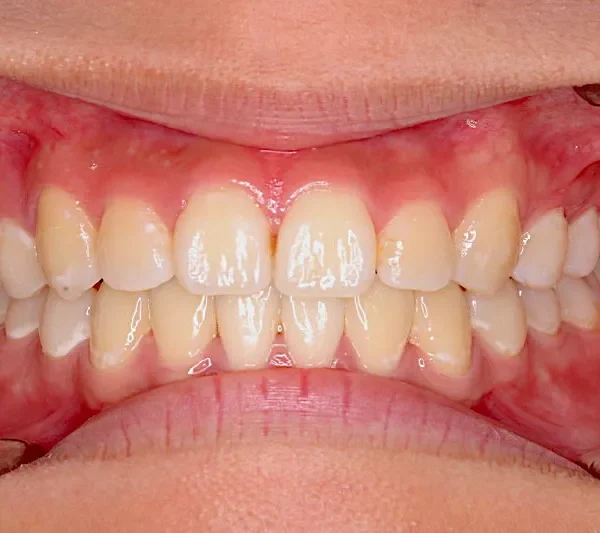

• 治療終了後

治療終了後

上下前から見える装置をつけ治療しました。歯は抜いてないです。

治療回数57回、6年9ヶ月の治療期間で矯正治療を終了しました。

主訴が改善され、ご満足頂きました。